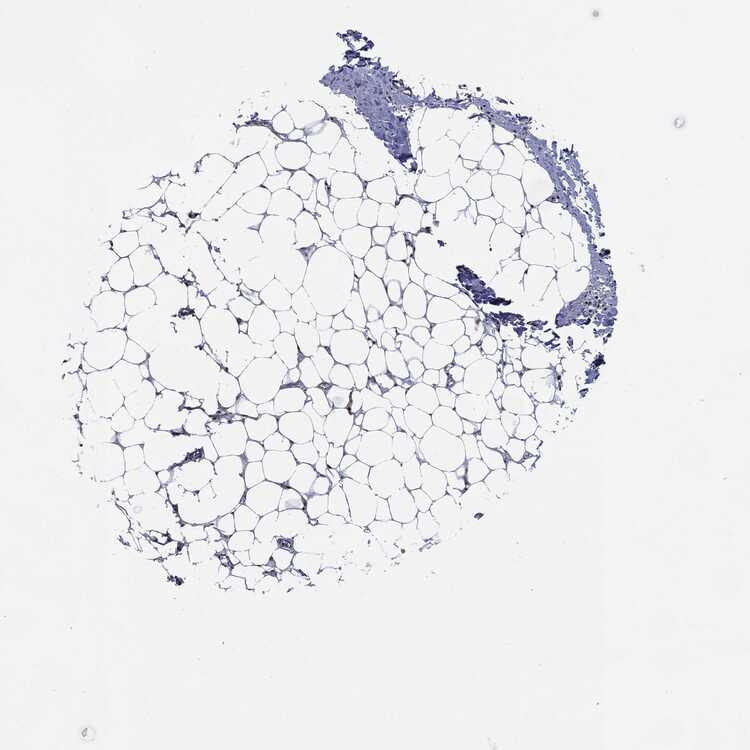

SOFT TISSUE 1 - Antibody stainingi

Antibody staining in the annotated cell types in the current human tissue is reported as not detected, low, medium, or high, based on conventional immunohistochemistry profiling in selected tissues. This score is based on the combination of the staining intensity and fraction of stained cells.

Each image is clickable and will lead to virtual microscopy that enables deeper exploration of all samples and also displays staining intensity scores, fraction scores and subcellular localization as well as patient and tissue information for each sample.

Antibody CAB004204Antibody CAB080295

Chondrocytes -Not detected

Fibroblasts MediumHigh

Peripheral nerve Low-